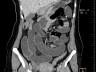

Case of the Week 25 2016 *39-year-old female with abdominal pain and vomiting. What is the most likely diagnosis? Answer Answer: Small bowel obstruction caused by intussusception produced by an ileal lipoma. Kategori:Cases Önceki yazı Case of the Week 21 2016 Sonraki yazı Case of the Week 26 2016